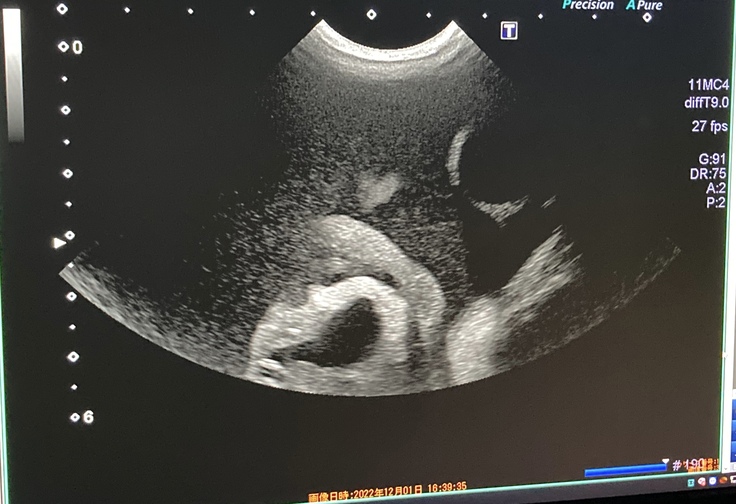

セカンドオピニオン病院 エコー結果↓(真っ黒なところが腹水だそうです)

ソナは腹水も溜まっていて、右腎臓の内側に2.5cm程の肉芽腫がある為、混合タイプでした。